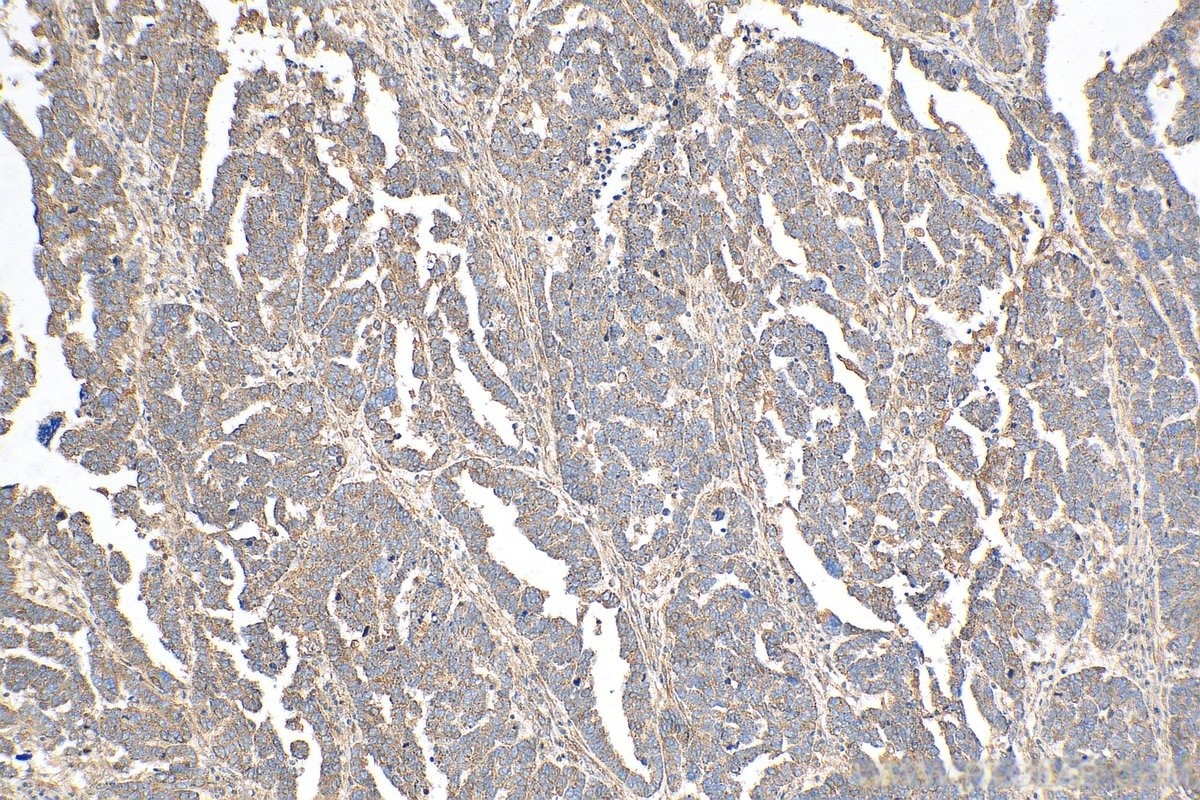

Immunohistochemical analysis of paraffin-embedded human ovary tumor tissue slide using (TXNIP antibody) at dilution of 1:200 (under 10x lens)

Immunohistochemical analysis of paraffin-embedded human ovary tumor tissue slide using (TXNIP antibody) at dilution of 1:200 (under 40x lens)